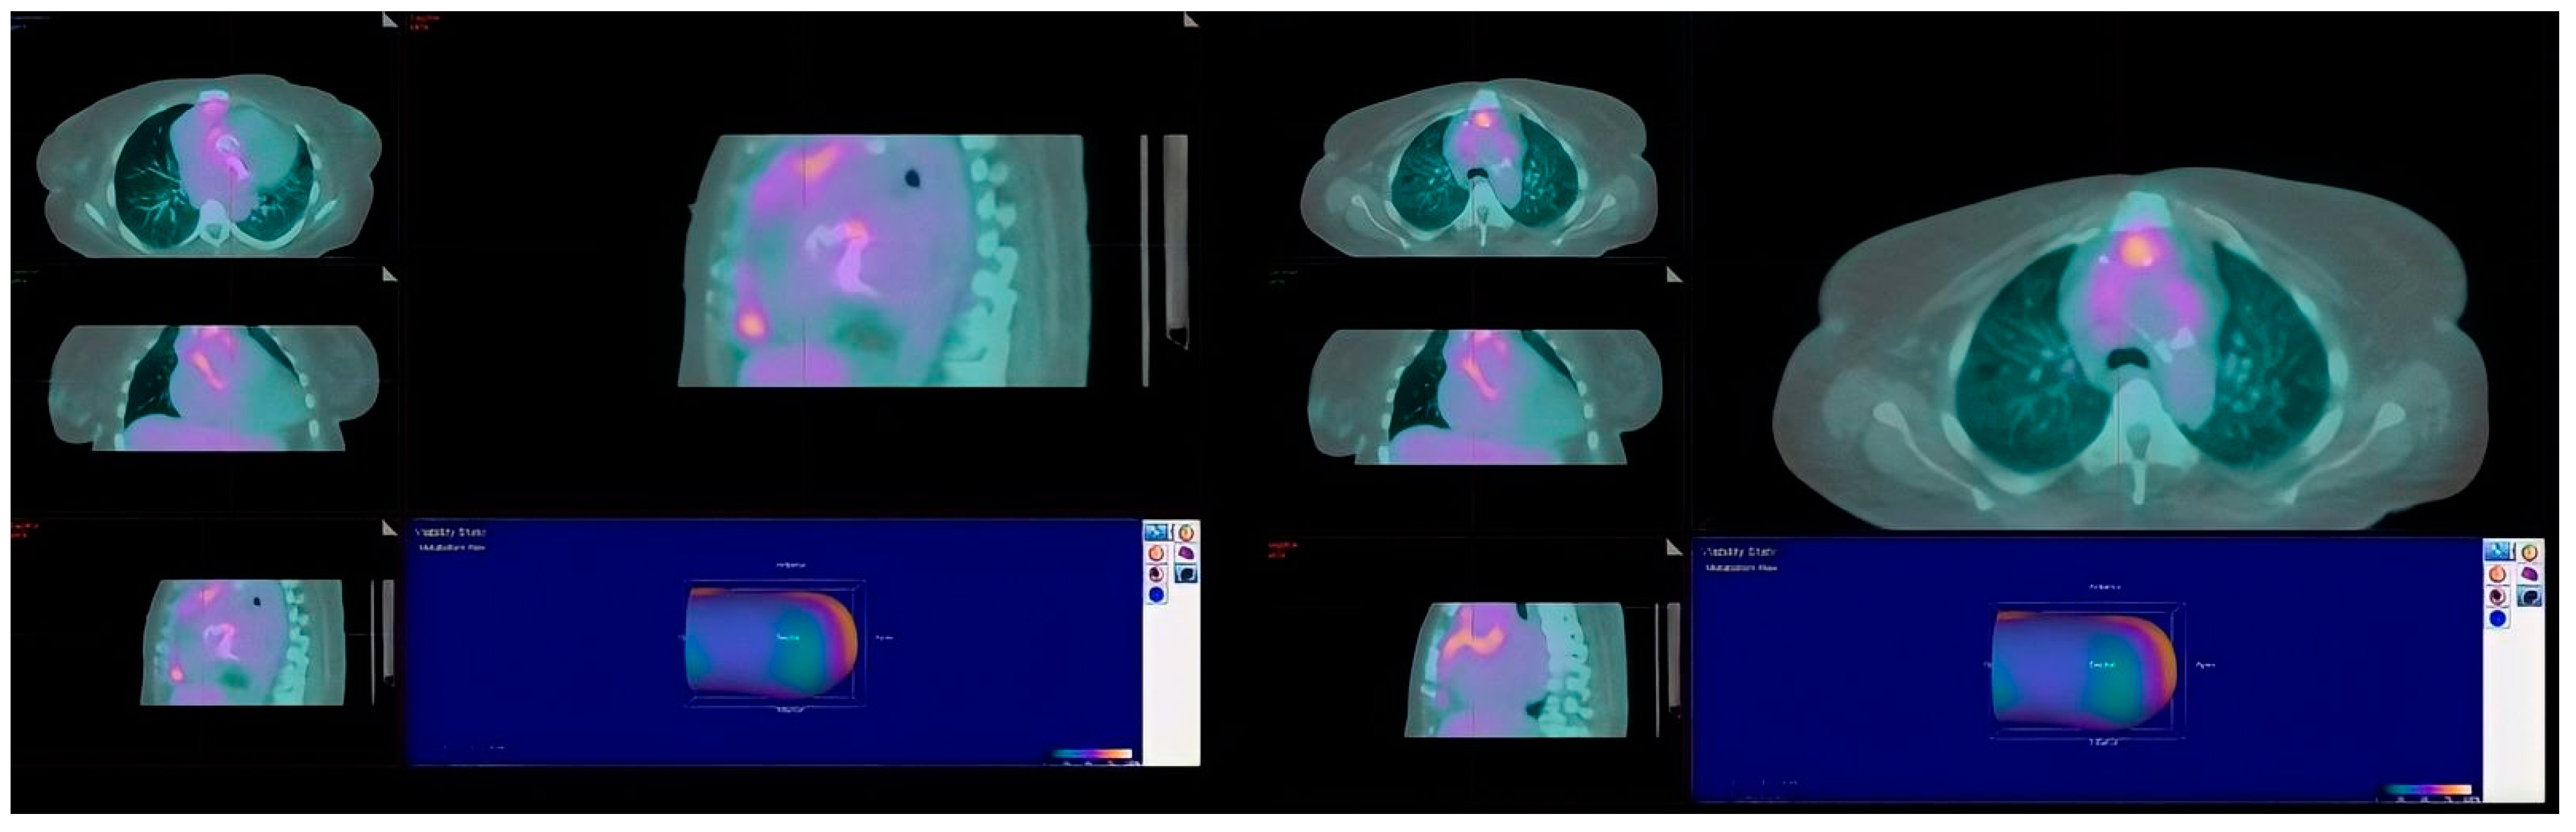

Refractory Salmonella Prosthetic Valve Endocarditis Complicated by Splenic Infarction and Aortic Pseudoaneurysm in a Patient with Double Prosthetic Valves: A Case Report

2. Case Presentation